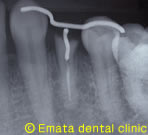

歯肉の下まで虫歯が進行しています。

治療中

エクストルージョンをおこないました。

歯が3ミリ以上、上に動いたのがわかりますね。